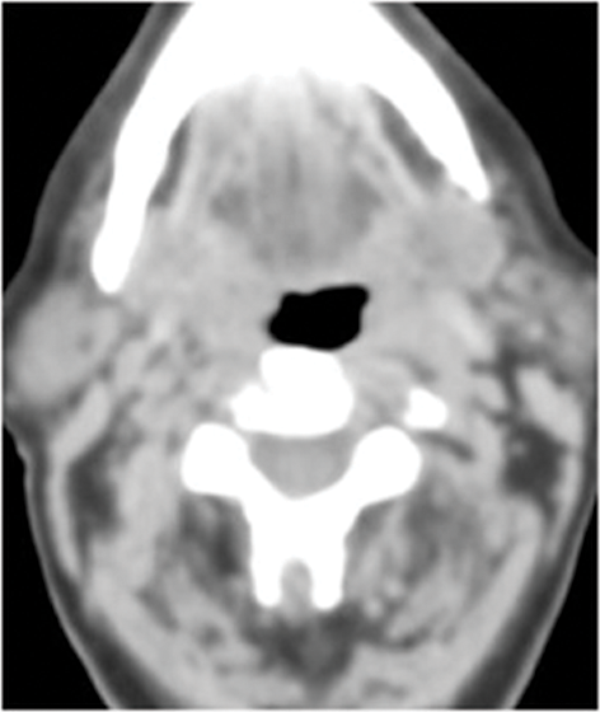

Figure 1: Patient who presented with an enlarged right level II node containing squamous cell carcinoma. No primary site was identified on usual assessment which included full clinical assessment and flexible fibre optic naso-endoscopy and head and neck MR. FDG PET-CT shows the primary site in right tonsil (arrow). Top pic = FDG, Middle pic = CT, Bottom pic =combined PET-CT.